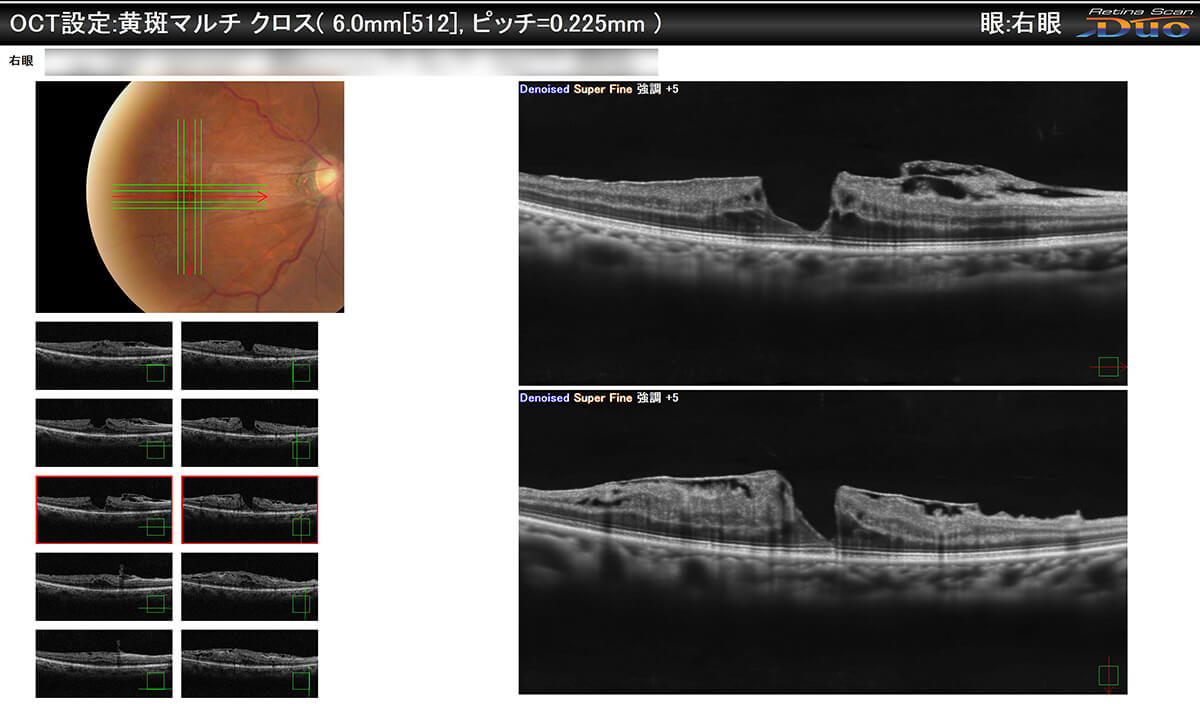

加齢黄斑変性には萎縮型・滲出型があります。OCT検査で判定します。

光干渉断層計(OCT)を導入しています。

当院の光干渉断層計(OCT)は、光干渉断層血管撮影(OCT-Angiography)が行えます。 これは、OCTの技術を応用した造影剤を必要としない新しい検査方法で、網膜の血流形態を診断するのに有用です。加齢黄斑変性症も早期に検出が可能です。

光干渉断層計(OCT・OCTA) Retina Scan Duo2 詳細はこちら

光干渉断層計(OCT・OCTA) Retina Scan Duo2